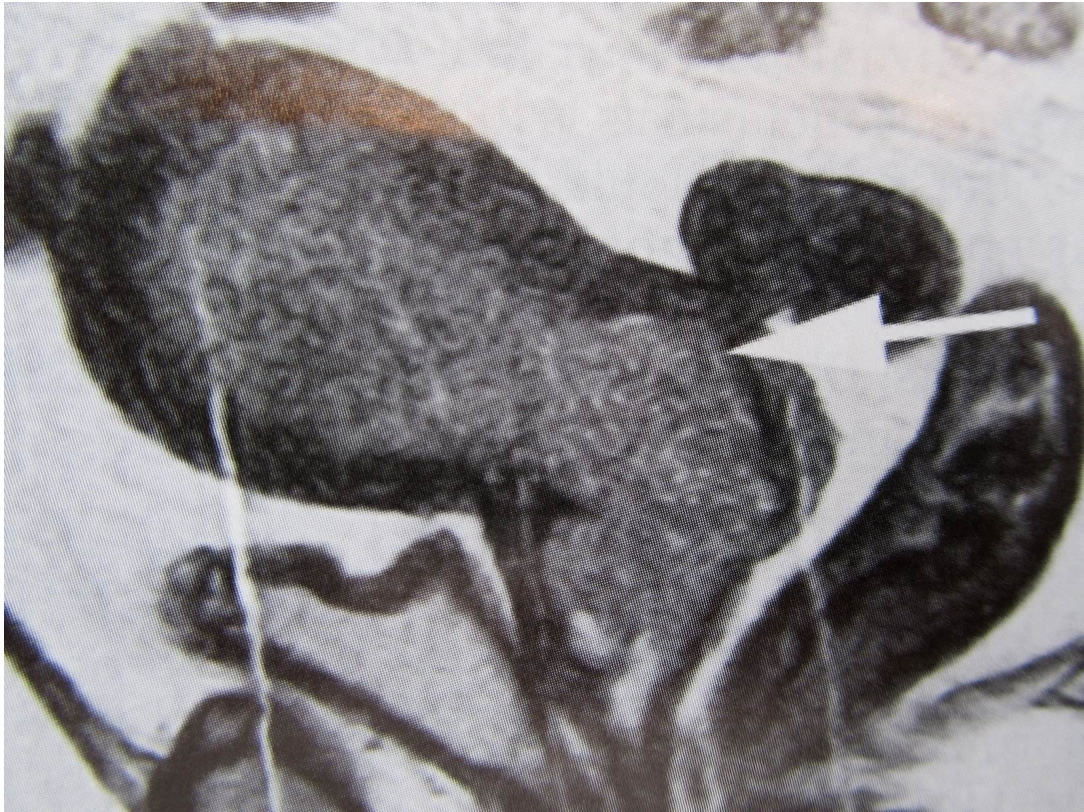

What this be?

Mass of rectum penetrating bladder wall